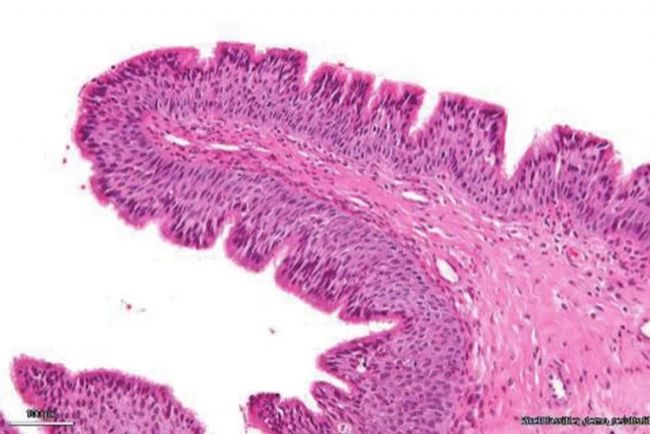

DM3000傳統(tǒng)病理染色明場成像,通過Aivia打開數(shù)據(jù)

Pixel Classifer進行細胞圈選與分割

基于細胞面積進行K-means聚類分析,同一顏色代表一種細胞群體

不同細胞群體按照面積大小進行數(shù)量的統(tǒng)計分布